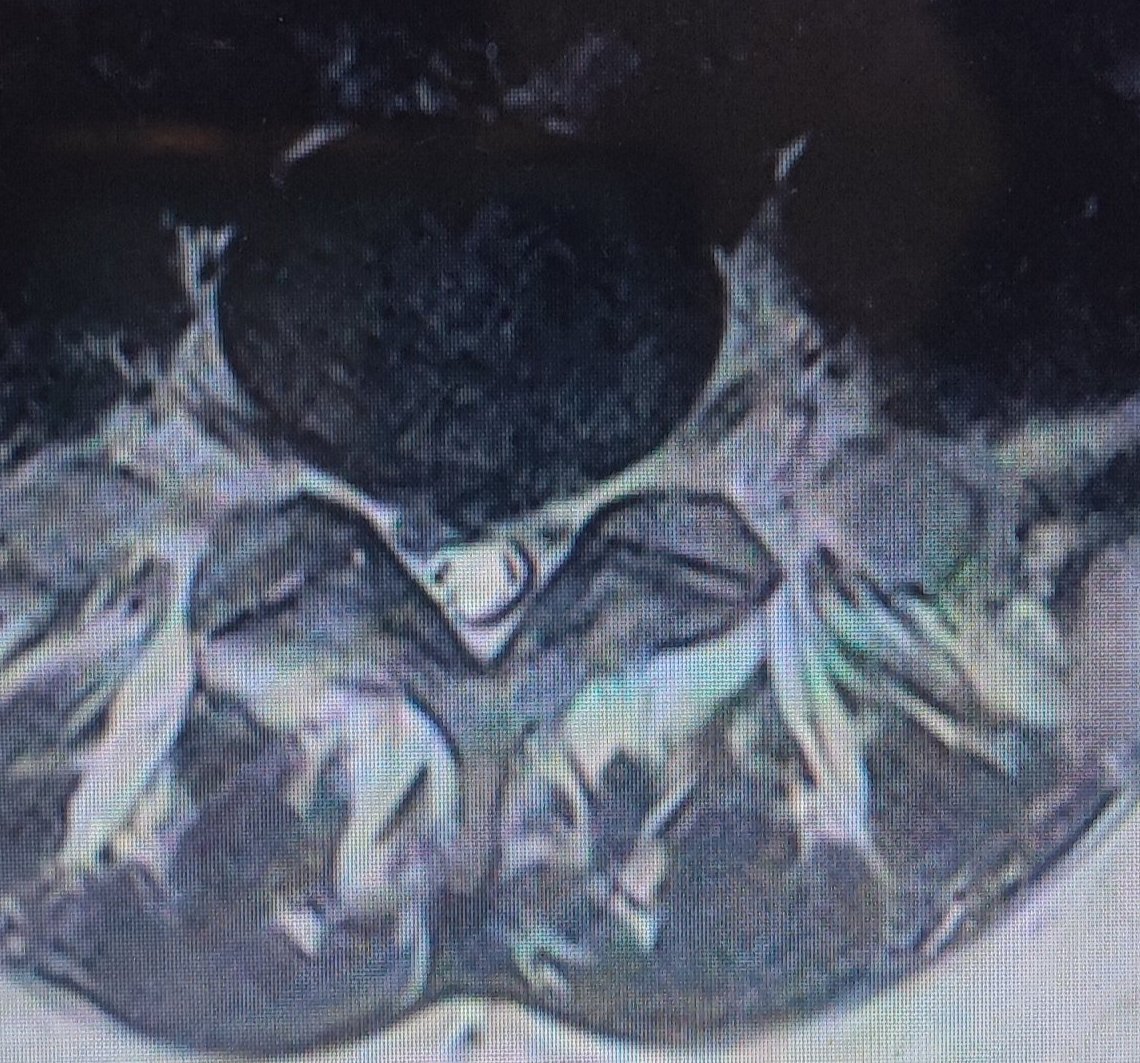

Може ли дискова протрузия да се излекува без операция?

Възможните лечения за облекчаване на болката при дискова херния включват физиотерапия, масажи, озонна терапия, дълбока осцилация и лекарства без рецепта. Освен това акупунктурата и манипулативната терапия могат да бъдат опция за справяне с болката. Формулярът обсъжда различни методи за облекчаване на болката, включително инжекции с кортикостероиди, лекарства като милгама, физиотерапия, физически упражнения и опит с различни лекарства като линефор/лирика и габагама. Най-ефективните методи за облекчаване на болката при дискова херния включват приемане на мускулен релаксант като мидокалм, витамини като милгама и магнезиев цитрат, физиотерапия, декомпресионни и стречинг упражнения, както и специална седалка с опора за гръбначния стълб.